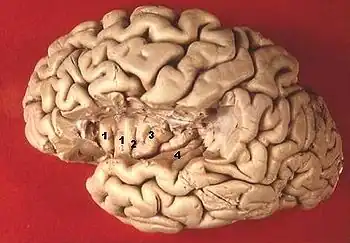

| (fig. 1) Coupe coronale | (fig. 2) Face supérieure de T1 après résection d'une partie des lobes frontal et pariétal |

![]() | |

| (fig.3) Vue de la face supérieure de T1 et de l'insula après résection d'une partie du lobe frontal et pariétal 1,2,3 : les cinq gyri de l'insula 4 : gyrus temporal transverse (de Heschl) | Coupe sagittale |